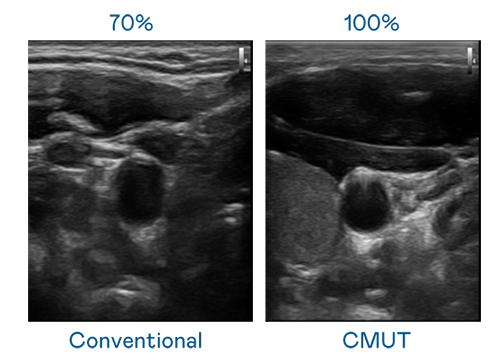

CMUT 技术是一种用电容式微机电元件来产生超音波讯号的技术。与传统 PZT 压电式技术相比,CMUT 频宽增加 30%,更宽频的超音波讯号让影像解析度大幅提升,是实现高影像品质医疗超音波扫描、促进精准医疗发展的关键技术。

超音波影像的解析度高低,首先取决于探头能发出的讯号频宽。免费看女生裸妆视频的app CMUT 可提供高清晰的超音波讯号,提供高频宽、高灵敏度、影像纹理细节更高的超音波影像,协助医护人员缩短影像判读时间及利用精准的医疗影像进行诊断。